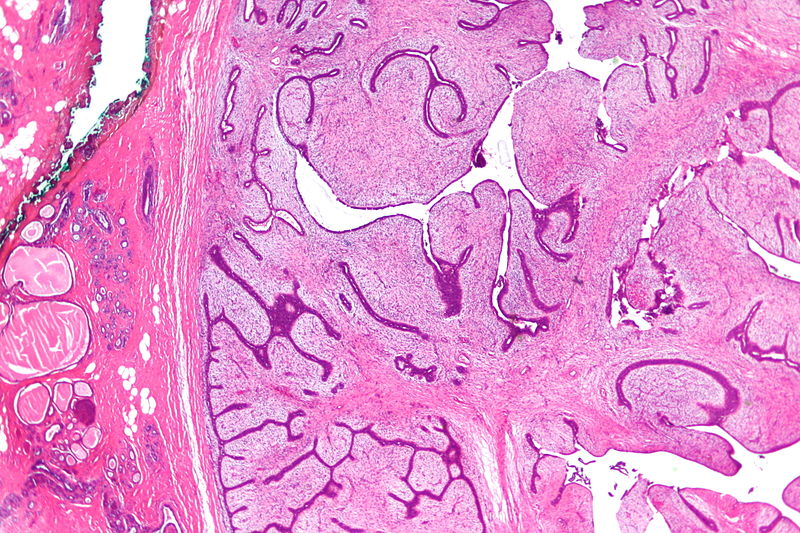

Phyllodes tumor is a tumor with an overgrowth of the fibrous component that resembles a fibroadenoma.

The histology of Phyllodes tumor shows leaf-like projections.

Phyllodes tumor is most frequently observed in postmenopausal women and.

In some very rare instances, Phyllodes tumor may become malignant.